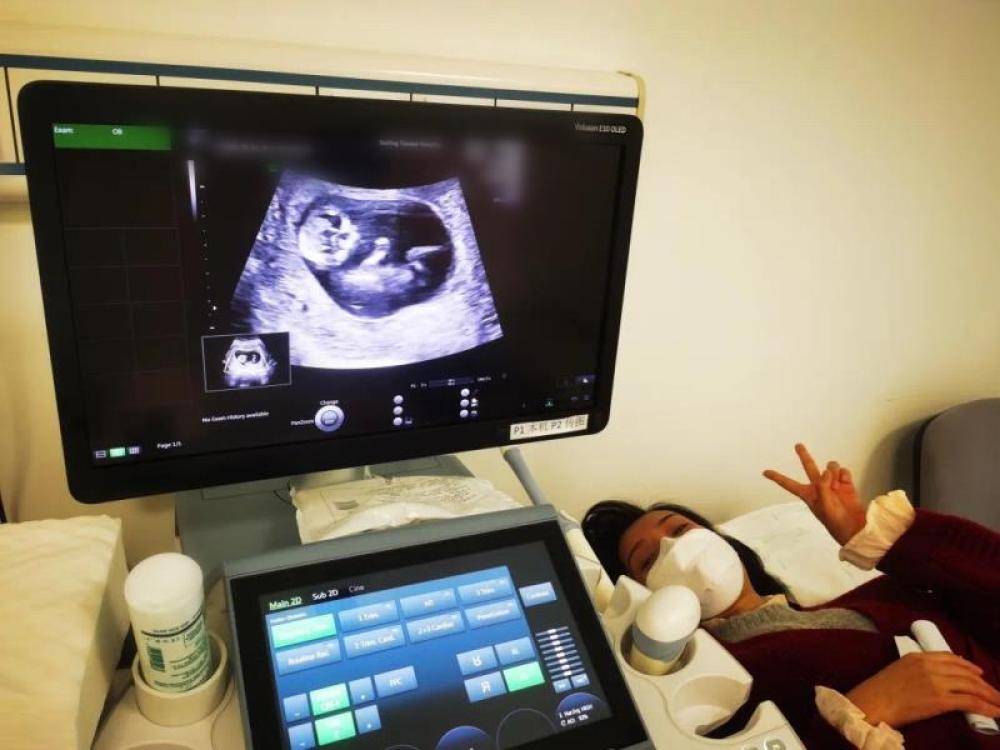

今天一早,妻子去醫院進行B超檢查,同事用手機拍攝下了B超顯示屏上的畫面,記錄下了這個87天的小家伙第一次“亮相”。

圖為北京天壇醫院袁磊愛人做B超檢查。

“袁磊,看看你們家寶寶,可愛嗎?”收到同事發來的視頻,第一眼就看哭了,身邊的同事看完視頻也哭了。

視頻里,這個小家伙好像聽到了外面的召喚,在媽媽的肚子里伸手、踢腿、翻身,用各種動作進行回應……看到他那小胳膊小腿,一種從未有過的幸福感不停地向上涌,眼淚怎么也控制不住。

其實在武漢這么多天,他一直就是我的牽掛,今天終于看到他了,那種感受真是又緊張又激動,雖然還看不清他的樣子,但是已經感受到他的活力。